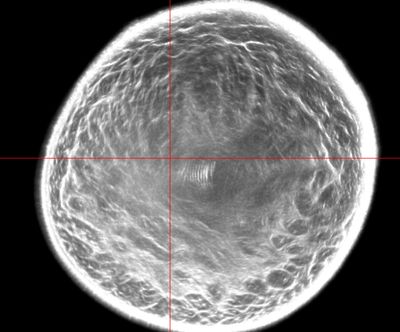

QT Imaging is an advanced breast imaging technology that uses Quantitative Transmission Ultrasound (QT) to create high-resolution, 3D images of breast tissue without radiation or compression. It is designed as a safer and more comfortable alternative to mammography while improving breast cancer detection, particularly in women with dense breast tissue.

🔹 True 3D Ultrasound Imaging

🔹 No Radiation, No Compression

🔹 Enhanced Detection for Dense Breasts

🔹 FDA Clearance

🔹 More Comfortable & Painless

🔹 Potential for Standalone Screening